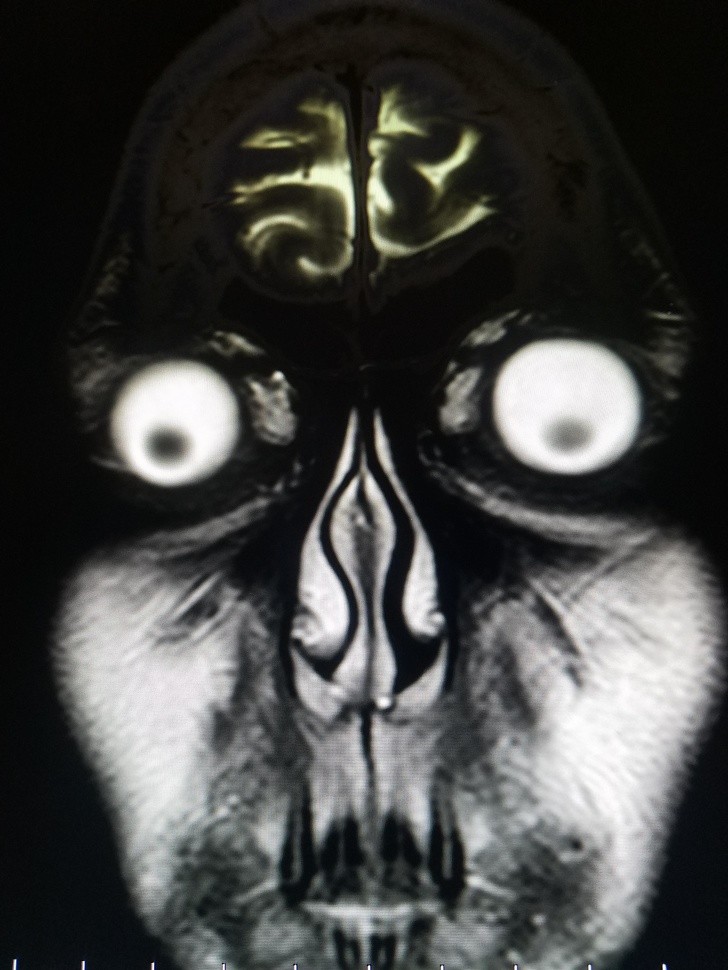

Ljudje smo resnično čudna bitja in se nam lahko zgodijo neverjetno bizarne stvari. Ti rentgenski posnetki bodo šokirali tudi tiste, ki mislijo, da so videli že vse.

Radiologi so tako že precej navajeni, da na rentgenskih posnetkih vidijo čudne stvari in nekatere izmed teh, ki smo jih za vas zbrali v galeriji, jih sploh niso presenetile. Tukaj je 15+ odštekanih in na trenutke šokantnih rentgenskih posnetkov.